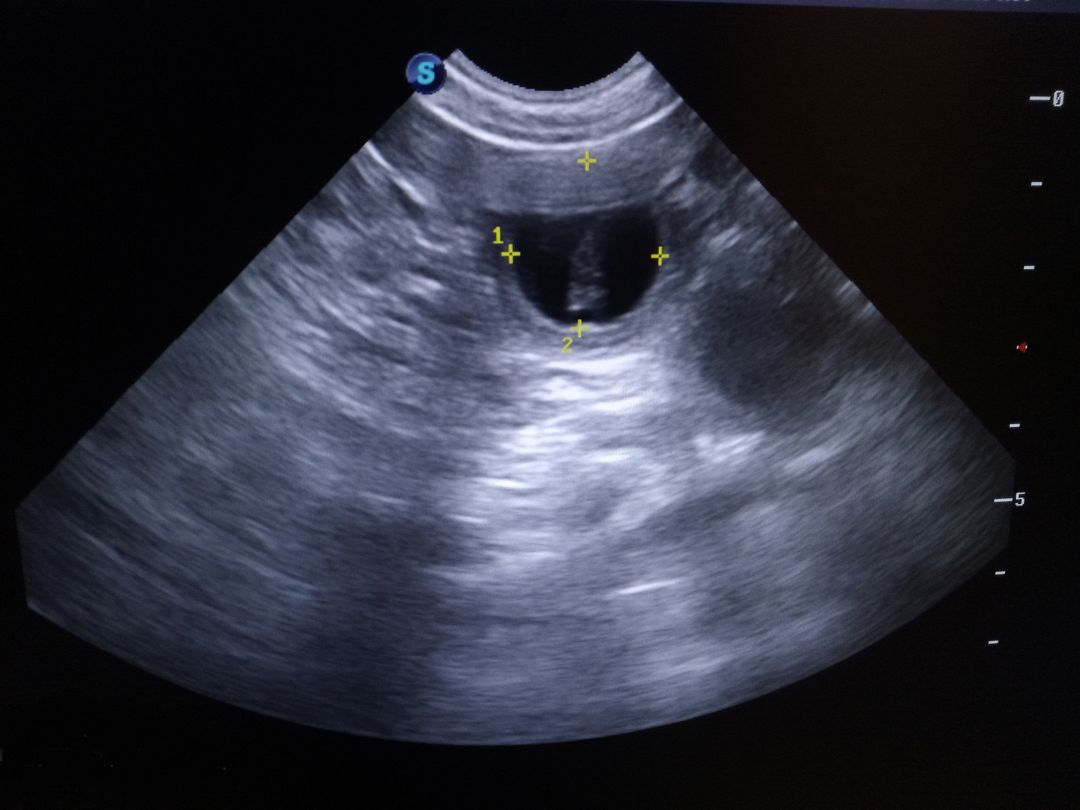

ciążę mnogą.

Technika się rozwija. Można zobaczyć coś co ma być samoyedkiem. Na razie, co prawda, mało to przypomina "chmurkę", ale trzeba w technikę wierzyć.